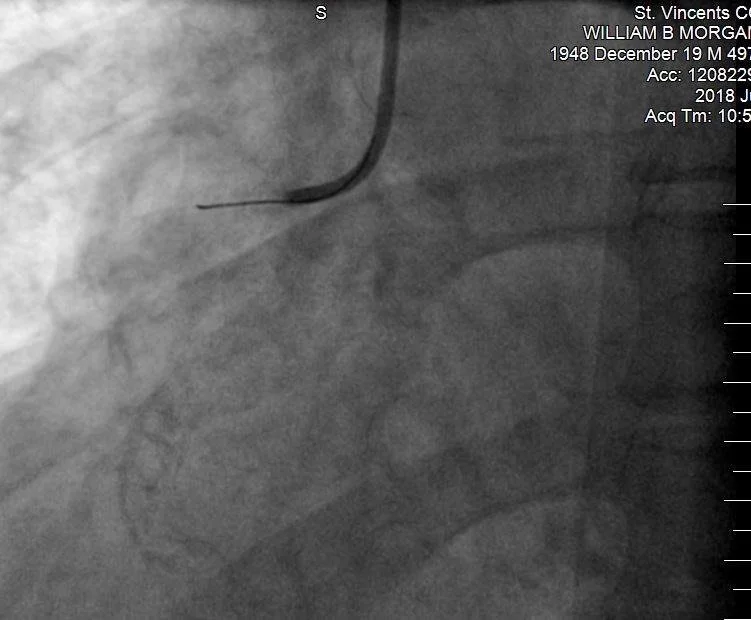

BILL’S HEART Early July, thanks to my keen personal physician Dr. Renee and competent cardiologist Dr. Jim, I was on the business end of a heart catheterization. I saw my heart on the screen after the catheter snaked its way into my cardio-sanctum (my term) to check out some suspicious artery issues. Bottom line: a couple prescriptions, no stents, needed. Dr. Jim actually nodded at the screen: ‘you’ve got a good heart.’